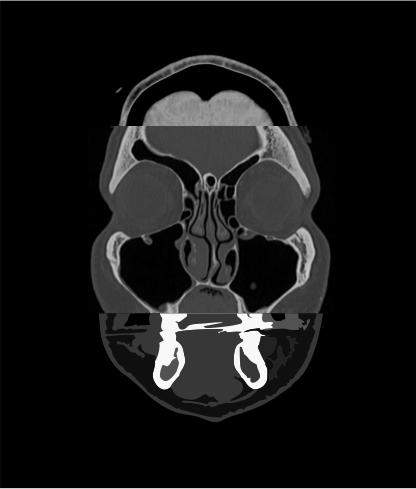

Axial, sagittal and coronal reformations with 2 mm thickness in bone (WW:4500, WL:450) and soft-tissue (WW:400, WL:40) window.